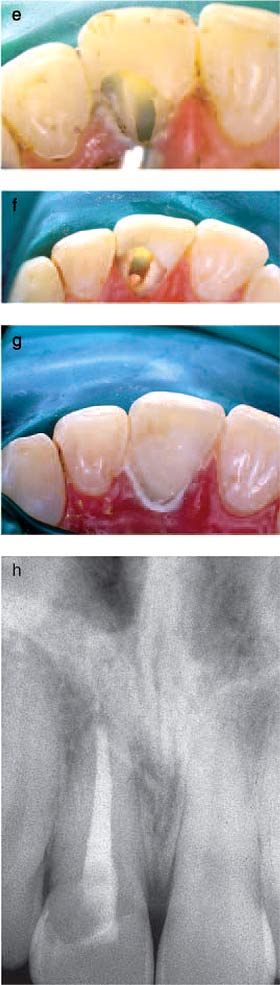

Fig. 18. (a) The maxillary right central incisor of a 21- year-old woman shows

a pink discoloration on the labial aspect of the crown. The tooth had been traumatized

9 years earlier. (b) A radiograph of the maxillary right central incisor reveals

an irregular radiolucency overlying the root canal with no obvious extensions

into the root canal. This invasive cervical resorptive lesion is classified as

Class 2. (c) After a protective application of glycerol to adjacent soft tissue,

a rubber dam ‘cuff’ has been placed for protection and isolation. This has been

supplemented with a glycerol-impregnated cotton roll placed in the labial sulcus.

(d) Trichloracetic acid on a small cotton pellet is applied to the resorptive

defect with slowly increasing pressure, so that the resorptive tissue within

the cavity undergoes coagulation necrosis. (e) The appearance of the tissue within

the resorptive defect following the application of trichloracetic acid indicates

tissue necrosis. The adjacent whitened gingival tissues indicate a limited zone

of coagulation necrosis. (f) Following curettage of the avascular tissue from

the resorption cavity, the glistening dentinal base of the cavity is revealed.

The incisal margin of the cavity has been smoothed with high-speed bur under

water spray. (g) A glass-ionomer restoration has been placed in the cavity, and

its surface has been protected with a light-activated unfilled bonded resin.

(h) Clinical appearance of the tooth 5 years postoperatively. The original glass-ionomer

cement has been faced with a resin composite restoration. (i) A 5-year follow-up

radiograph of the maxillary right central incisor shows no evidence of periapical

pathosis or extension of the treated resorptive lesion. From (23). Reproduced

with permission from

Quintessence Publishing.